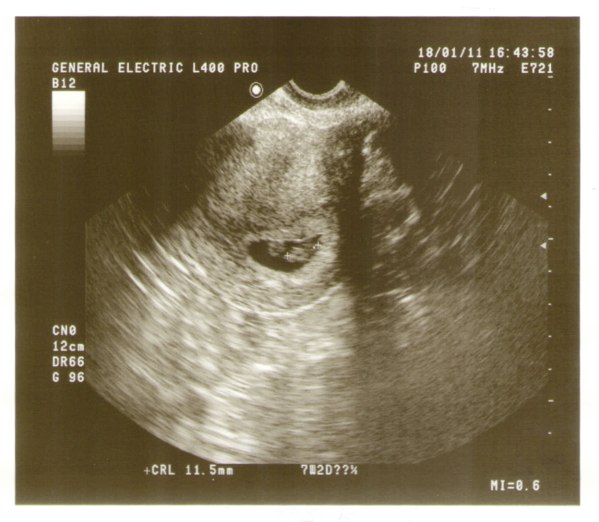

Embereknél az egypetéjű ikrek esetében a petesejt első 14 napjában bekövetkezik a szétválás ez után már nem. Azért mert az egypetéjű ikrek mint az elnevezés is utal rá ugyanabból a megtermékenyített petesejtből fejlődnek ki csak kettéválnak. Napon történik akkor a magzatok méhlepénye közös de külön burokban növekszenek mono di ikrek. Az egyikük sienna olyan betegségben szenvedett ami törpenövést okozott.